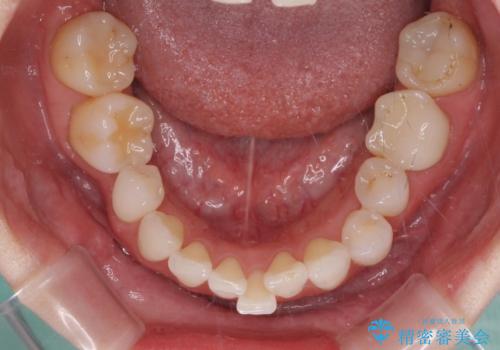

- 全体的なデコボコと、奥歯の欠損を放置した結果倒れ込んだ奥歯などを気にして来院された患者様です。

ワイヤー矯正の方が理想的な仕上がりとできる状態でしたが、上顎前歯にクラウンが装着されているため、インビザラインにて矯正治療を行うこととしました。

欠損部位は傾斜歯軸を起き上がらせることができたため、オールセラミッククブリッジにて補綴治療を行いました。